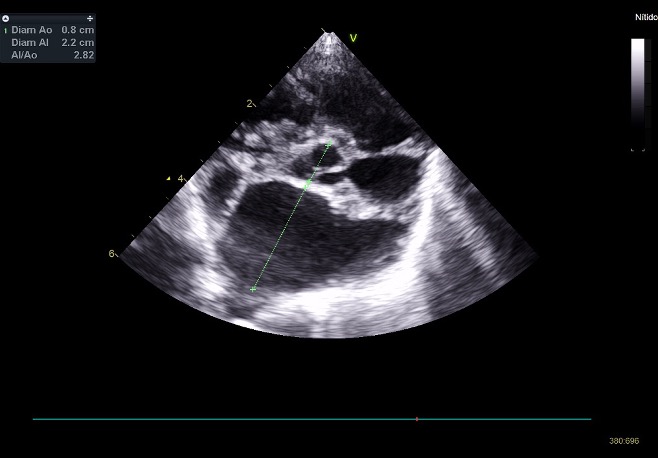

¿Y cómo la evaluamos en la clínica?

Se evalúa principalmente con ecocardiografía:

Flujo transmitral (Doppler pulsado): relación E/A, tiempo de desaceleración.

Haz clic en la imagen para obtener una vista más ampliada

Doppler tisular (TDI): onda e’ (relajación) y E/e’ (estimación de presiones de llenado).

Aurícula izquierda (LA/Ao): refleja cronicidad de la sobrecarga.

Flujo venoso pulmonar (si es posible).

En la disfunción diastólica, el problema está en el llenado ventricular alterado debid

o a rigidez y/o alteraciones estructurales. Y su principal signo clínico es la congestión a nivel pulmonar (si el problema es izquierdo) o abdominal (ascitis) si es del lado derecho.